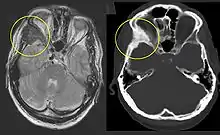

On x-ray, fibrous dysplasia appears as bubbly lytic lesions, or a ground glass appearance. Computerized tomography (CT) or magnetic resonance imaging (MRI) scans may be used to determine how extensively bones are affected. CT can better demonstrate the typical "ground glass" appearance, which is a highly specific radiological finding, while MRI can show cystic areas with fluid contents.[14] A bone scan uses radioactive tracers, which are injected into your bloodstream. The damaged parts of bones take up more of the tracer, which show up more brightly on the scan. A biopsy, which uses a hollow needle to remove a small piece of the affected bone for laboratory analysis, can diagnose fibrous dysplasia definitely.